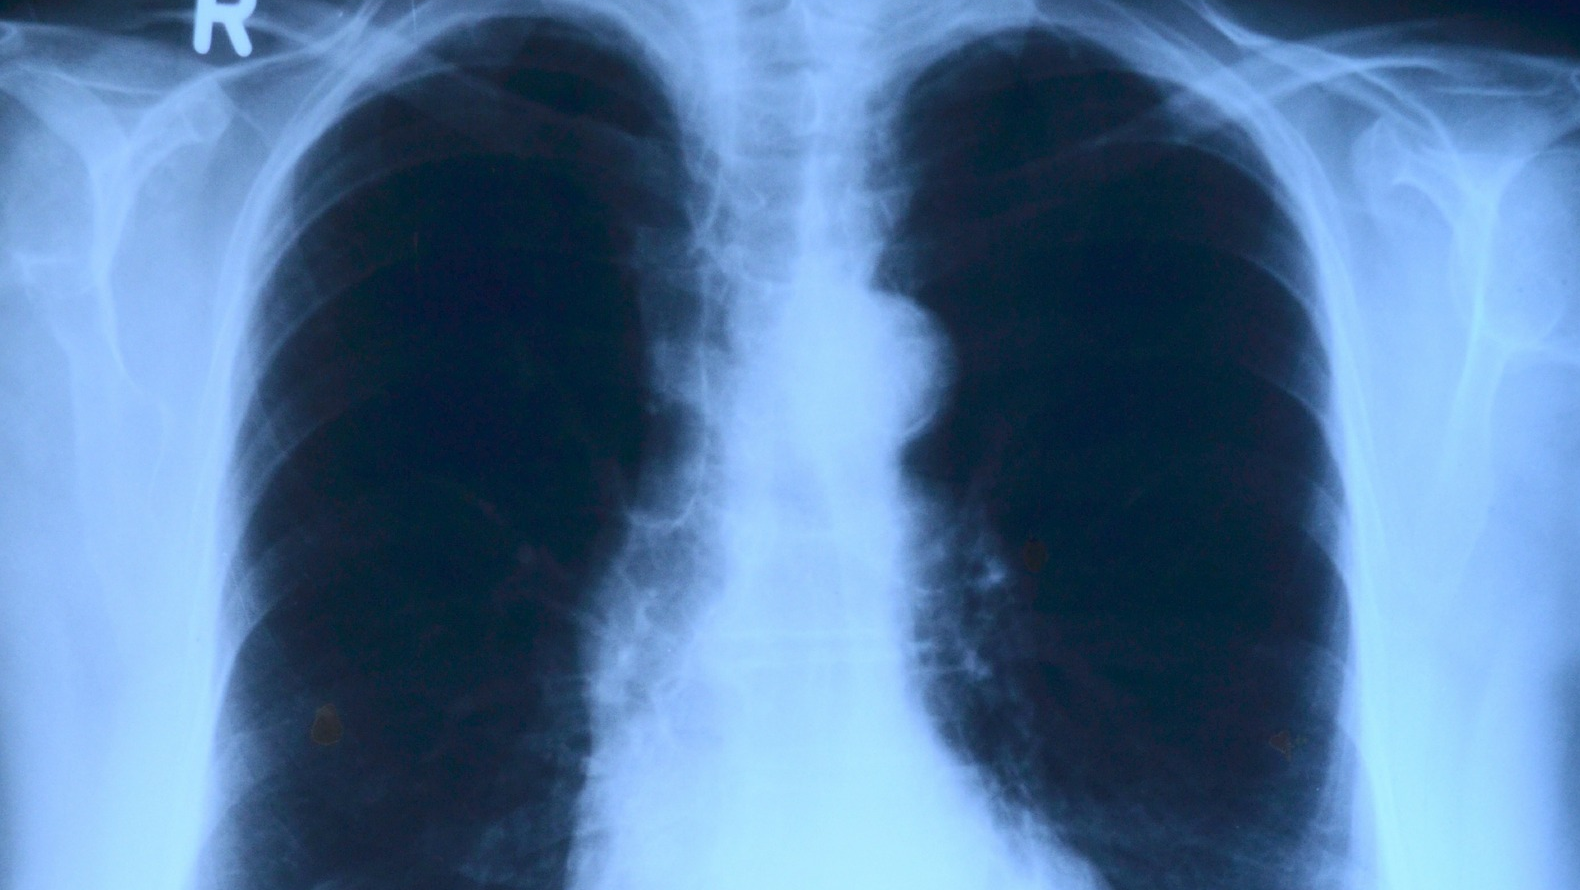

Lung cancer is the most common cancer type and the leading cause of cancer-related deaths worldwide. In the U.S., approximately 229,000 adults will be diagnosed with lung cancer in 2020, of which 76 percent of cases will be non-small cell lung cancer. Approximately 20 percent of patients with non-small cell lung cancer will have epidermal growth factor receptor (EGFR) mutations, which are mutations on a protein that causes rapid cell growth, and consequently, helps cancer spread.